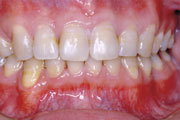

症例1:乱杭歯(叢生)